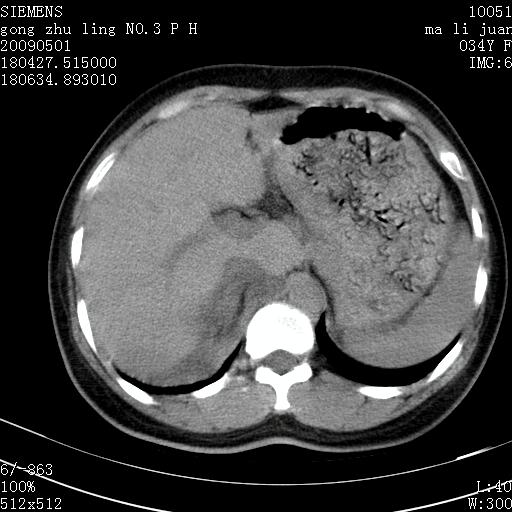

标题: CT19733:右肾碎裂 [打印本页]

标题: CT19733:右肾碎裂

青年女性,骑摩托车摔伤。

右肾碎裂伤,包膜下血肿。

术中仅见右肾碎裂,肾蒂血管未见断裂。

支持 右肾破裂伴肾包膜下及肾周血肿。

右肾破裂并右侧腹膜后间隙出血。